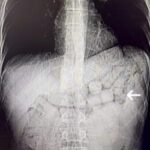

Selim KAYA/DİYARBAKIR, -Diyarbakır’da otogar alanında gözaltına alınan iki İran uyruklu şüphelinin, hastanede yapılan muayenelerinde mide ve bağırsaklarından 91 kapsül metamfetamin olduğu belirlenerek, toplamda 807,15 gram uyuşturucu madde ele geçirildi. Şüpheliler, tutuklandı.

İl Emniyet Müdürlüğü Narkotik Suçlarla Mücadele Şube Müdürlüğü ekipleri, İran’dan Türkiye’ye uyuşturucu madde taşınacağına dair bilgi aldı. Diyarbakır otogarında takibe alınan iki şüpheli, 14 Ocak tarihinde gerçekleştirilen bir operasyonla yakalandı. Şüphelilerin maddenin yutma yöntemiyle taşındığı değerlendirildiği için hastaneye gönderildi. Yapılan tomografi tetkiklerinde, mide ve bağırsaklarda yabancı cisimlerin bulunduğu tespit edildi. Üç gün süren tıbbi gözlemlerin ardından, yapılan müdahale ile 91 kapsül halinde 807,15 gram metamfetamin çıkarıldı. Adli süreçten geçmek üzere mahkemeye sevk edilen şüpheliler, tutuklama kararı aldı.